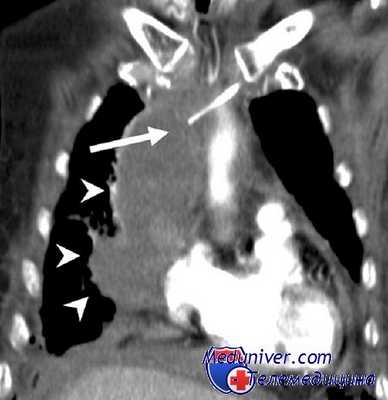

КТ ОГК. Массивное объемное образование верхнего средостения с объемным воздействием на трахею, исходящее из щитовидной железы.